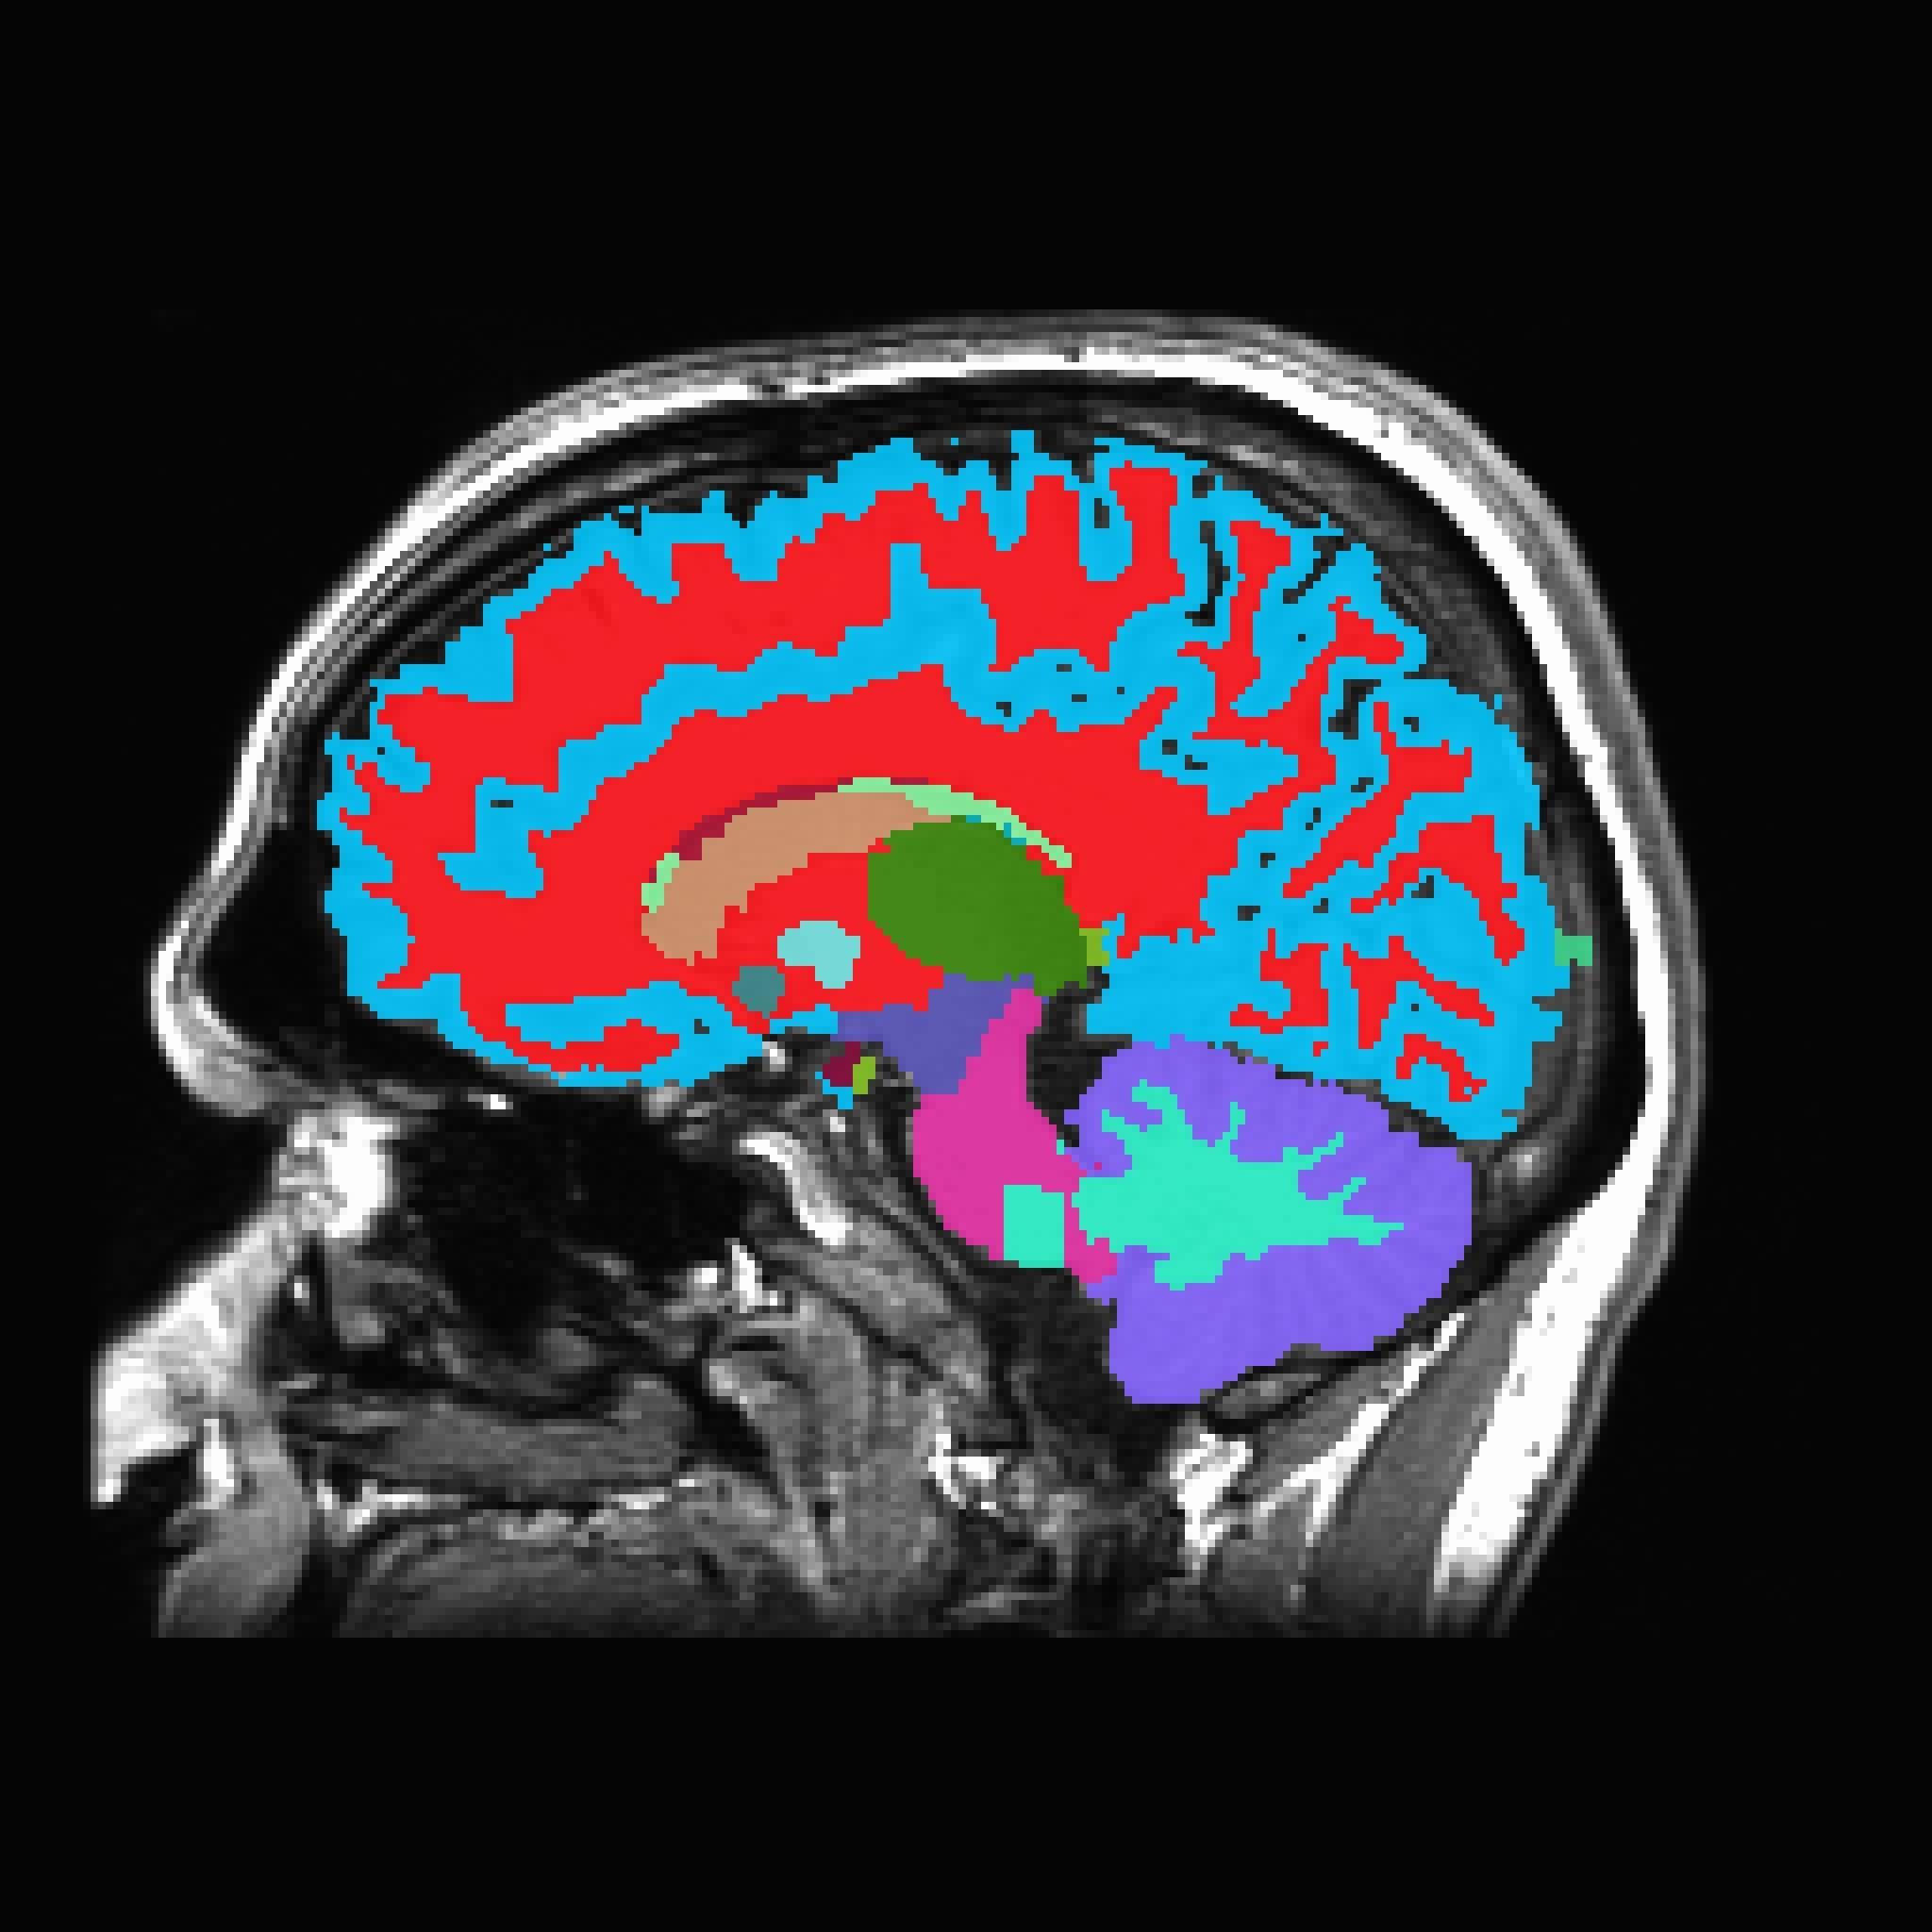

只需一次头部核磁共振成像(MRI)就能检测衰老速度,并预测未来几年患痴呆症和残疾的风险,这样的工具有望成为健康风险预警和干预的新手段。图片来源:杜克大学

在此基础上,团队利用860名参与者在45岁时采集的脑部核磁共振图像,训练出一种人工智能(AI)模型,名为“DunedinPACNI”(达尼丁图像脑龄模型)。该模型只需一张脑部扫描图像,即可估算个体的衰老速度。